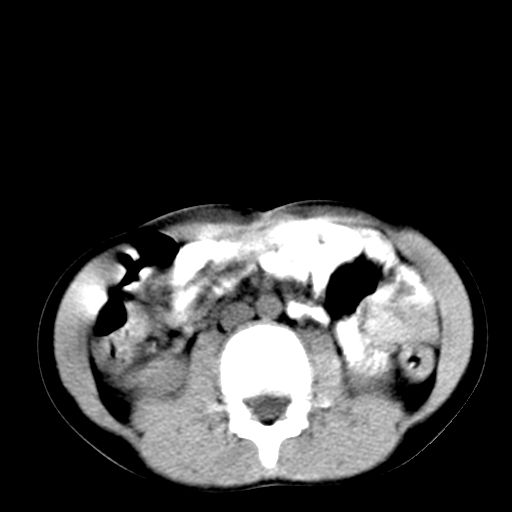

腹部好象未见异常。

腹部ct平扫未见明确异常

腹部ct平扫不能提示哪里有病变。